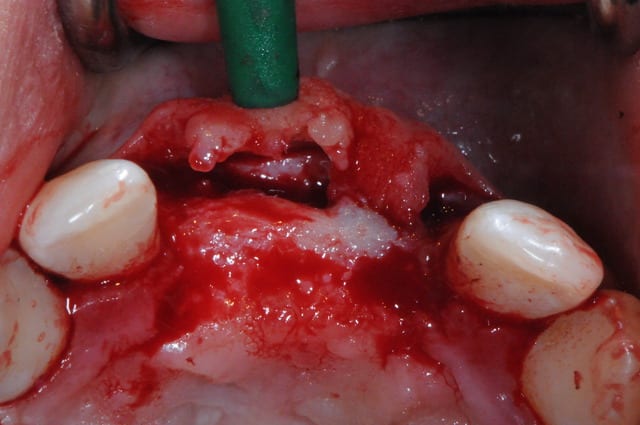

juste pour le plaisir des yeux...

j'étais hier à Strasbourg dans une formation avec Fouad Khoury.

génial ce type!

De quel type de greffons s'agit-il?

Biobank ?

oui biobank, je pense, mais plus simple; il y avait non?

Et par dessus ? des granulés de biooss ? Par dessus le biooss ? Un steak de PRF ?

oui biobank et granules de biobank par dessus.

la prochaine fois je fais à partir d'un ramique, ça coûte moins cher.